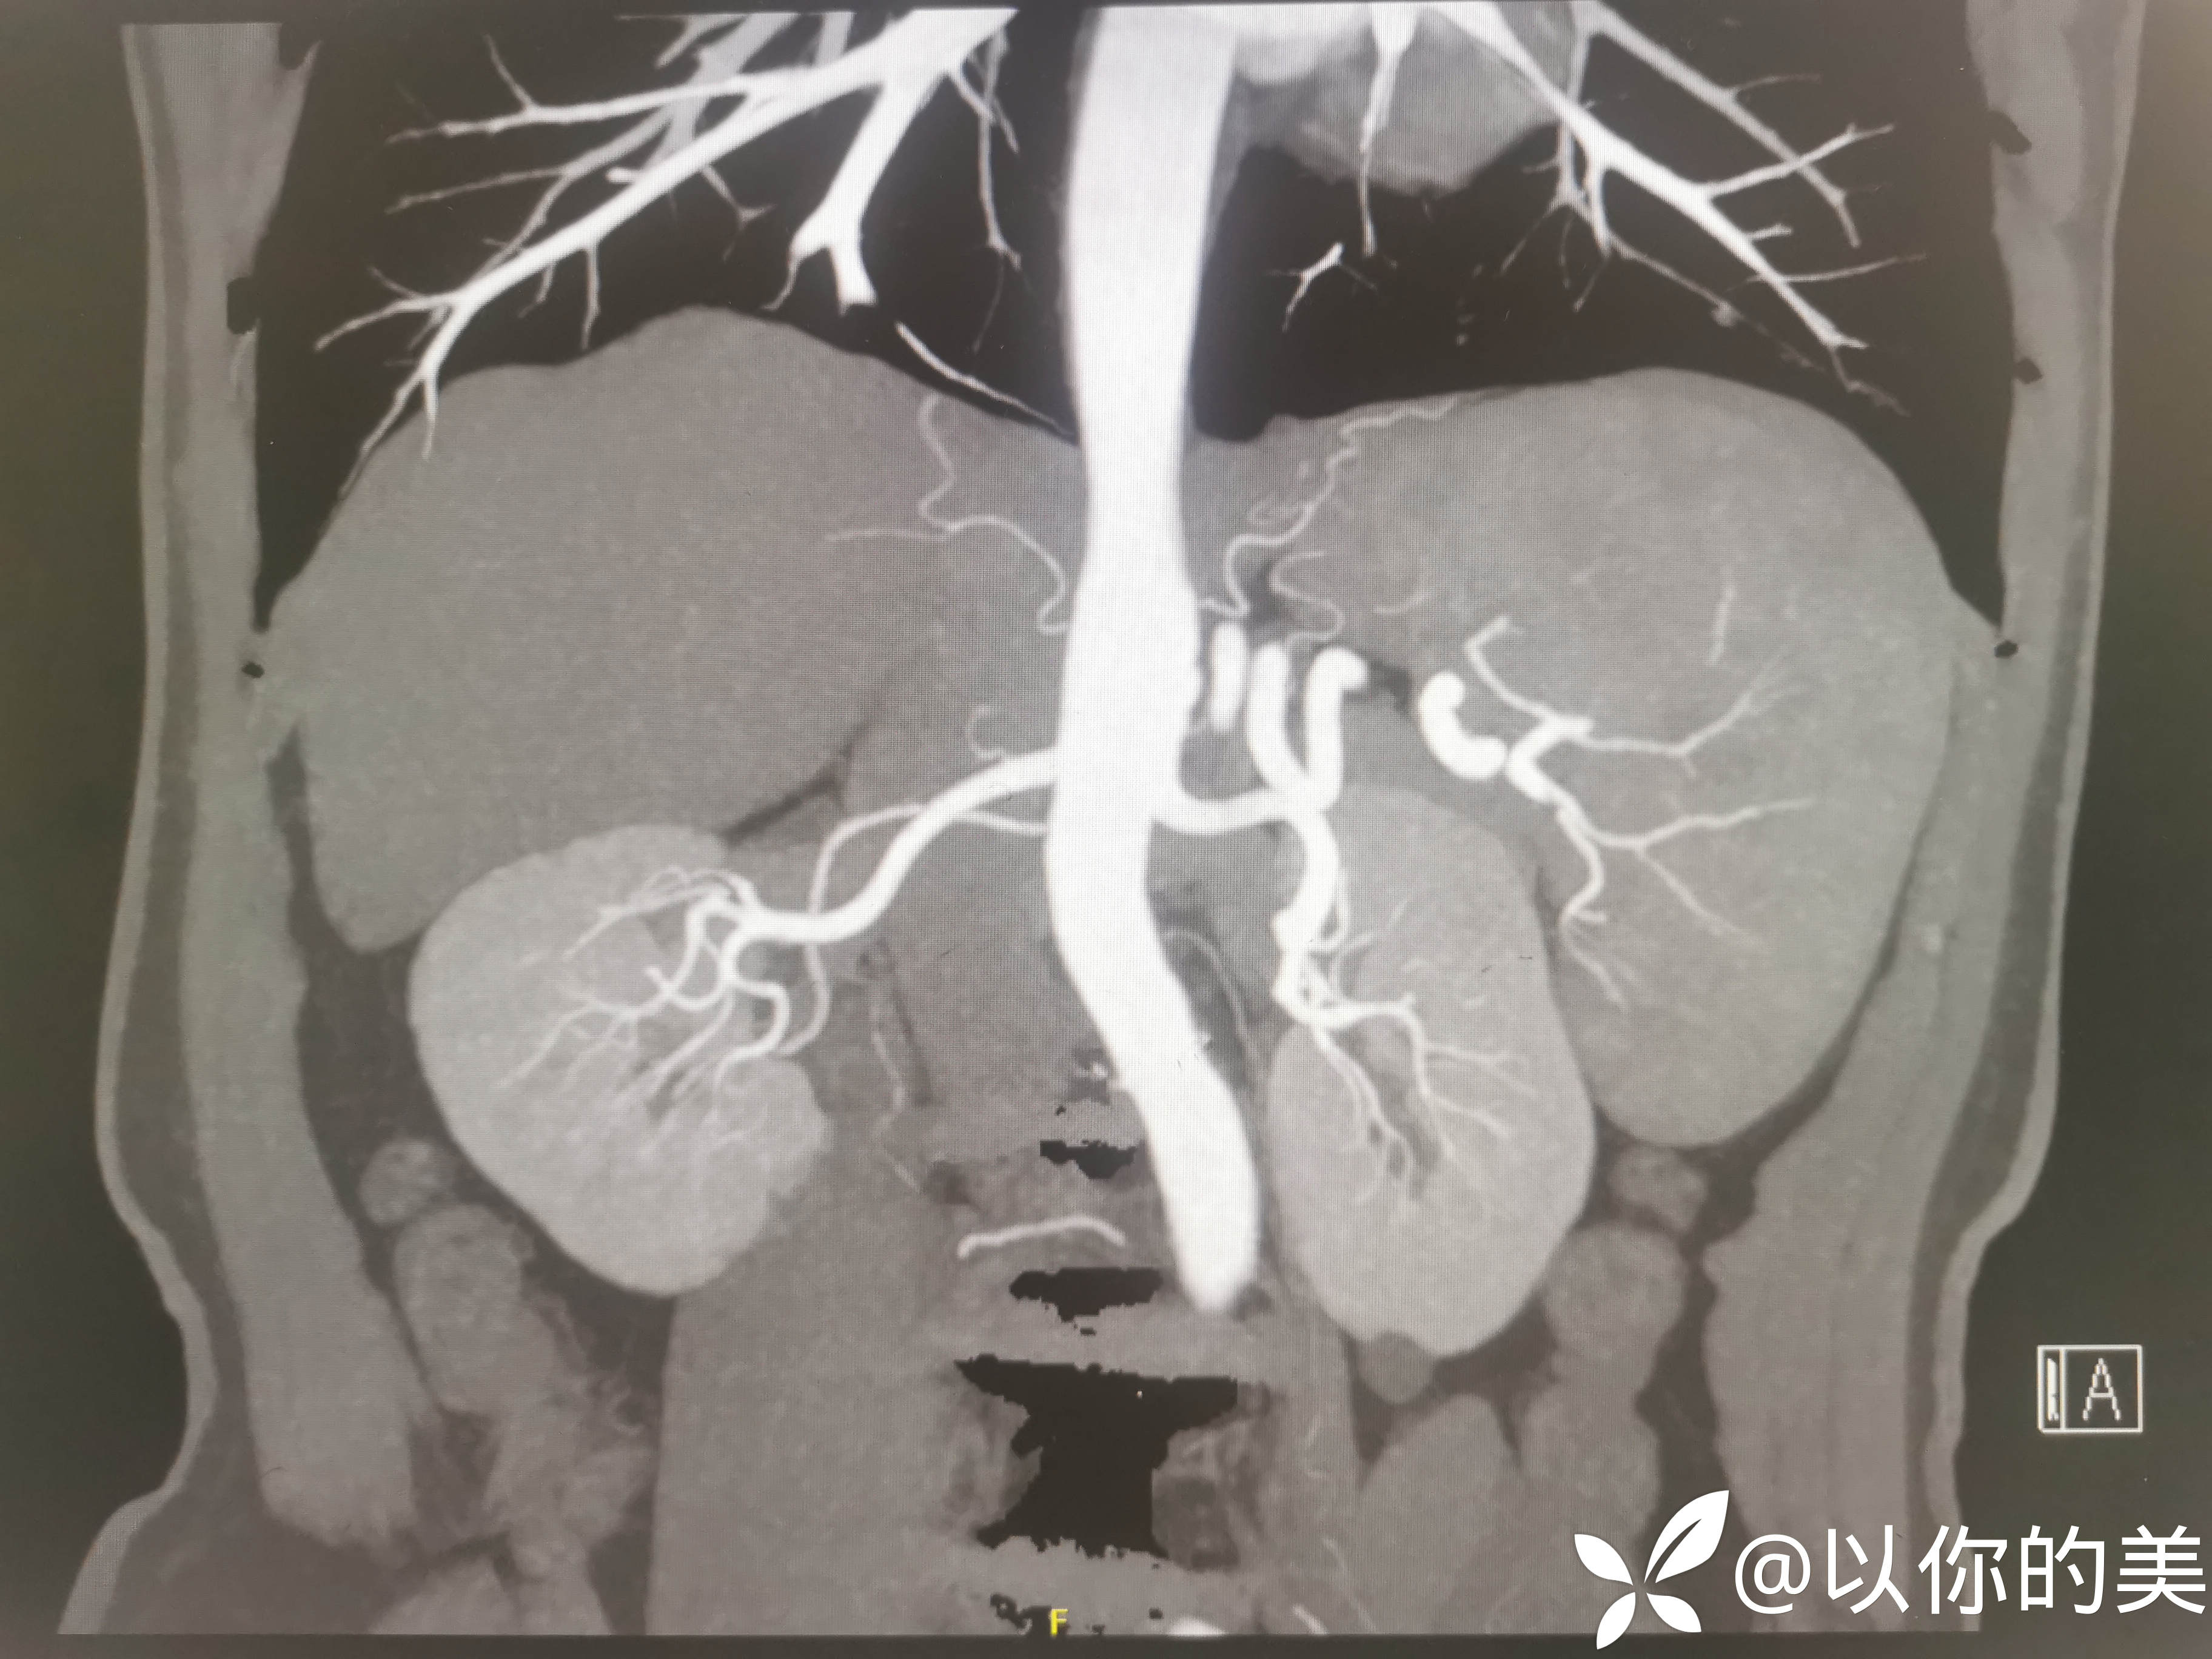

肾血管CTA:

肾血管CTA有无异常,行肾血管CTA意义何在?